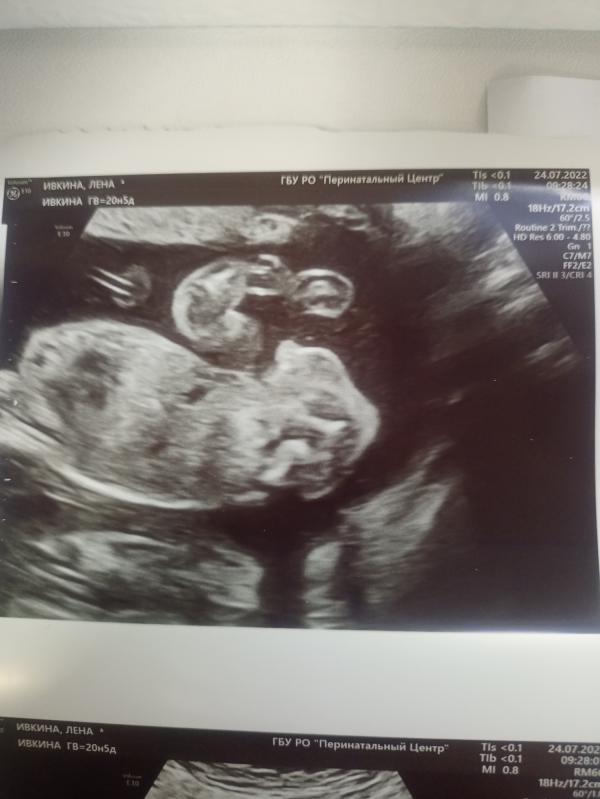

Дамы. Сегодня была на 2 скрининге сказали, что будет мальчик. Я думала будет доча. Подскажите,а сейчас дают направление на 3 скрининг?